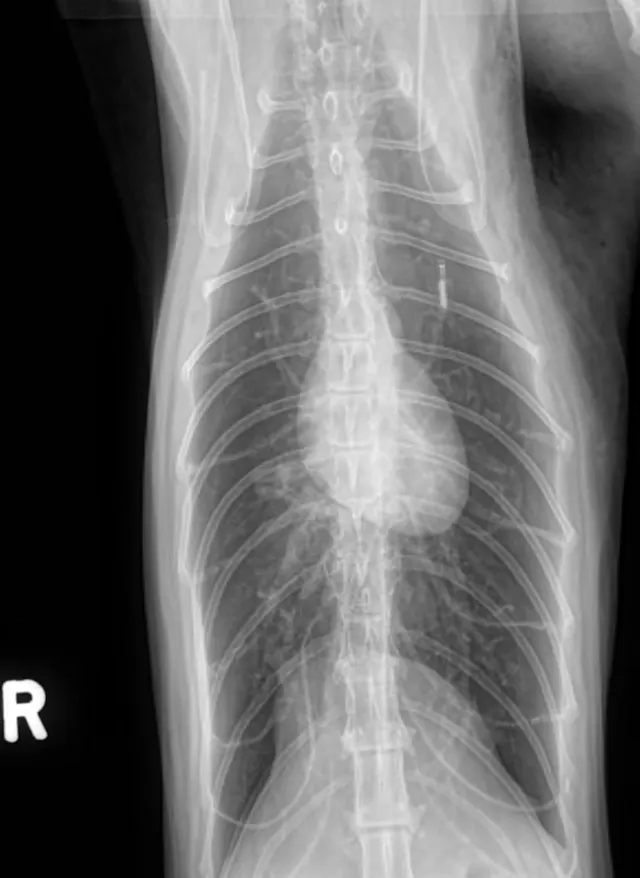

• Thoracic radiographs (3 views): Initial interpretation by overnight doctors was significant elevation of the cardiac silhouette from the sternum (moderate pneumothorax); diffuse bronchial pattern; moderate to severe subcutaneous emphysema of the left axilla. (See Radiographs)

The cat initially presented with a fever and lethargy; then developed acute dyspnea while hospitalized. The diagnosis and decision to treat for pneumothorax was an unfortunate misstep. The films taken upon referral are consistent with a bronchial pattern and show evidence of overinflation. Lung tissue is present throughout all lung fields and, although the cardiac silhouette is elevated, this is due to air trapping within the alveoli and not a pneumothorax. In general, a ventrodorsal view is good for confirming the presence of a pneumothorax: there would be black areas where the lung is pulled away from the chest wall as a result of air in the pleural space. In these films, lung tissue can be seen all the way to the edges of the thoracic cavity. As a side note, spontaneous pneumothorax has been reported in asthmatic cats, so it is not out of the realm of possibility.1

Radiographic Interpretation

Pneumothorax was diagnosed here based on the elevation of the heart from the sternum, which can be one of the signs of pneumothorax. However, it is extremely important to look at the entire radiograph.  In these, (see images) the lung fields can be followed to the edge of the chest cavity on both the lateral and ventrodorsal views: there is no air surrounding the lung lobes. Although the heart looks raised, the area ventral to the heart on the lateral images shows a soft tissue opacity (possibly fat), not air. The lungs are hyperinflated, which is consistent with primary lung disease and not a typical sign of pneumothorax.